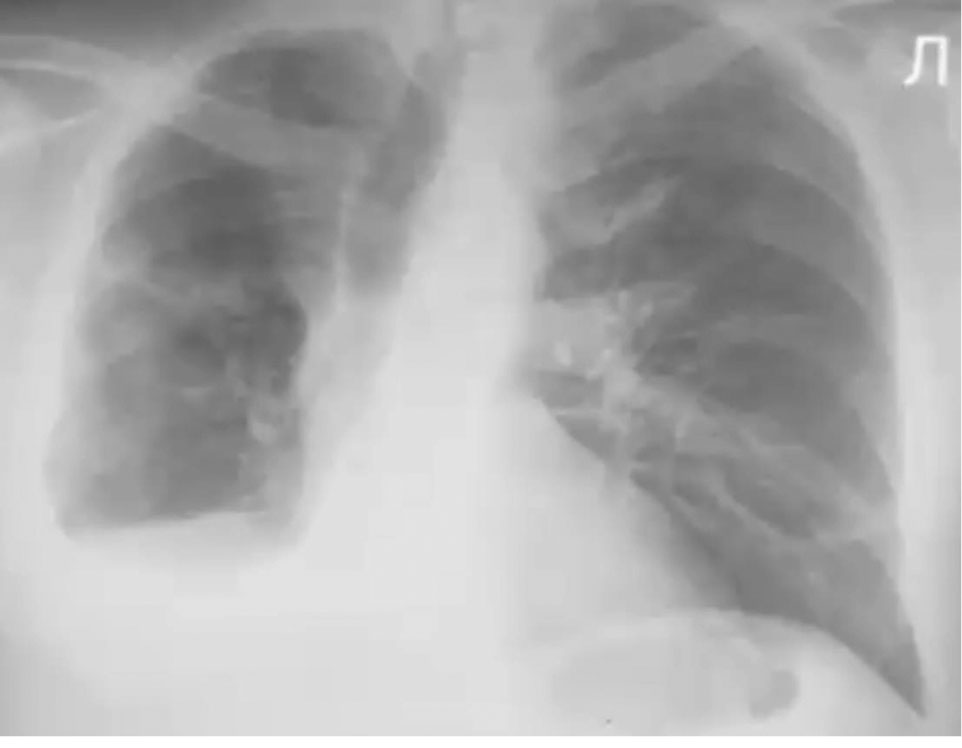

После окончания реабилитации был выполнен рентген-контроль (рис. 4). Очагов и фокусов уплотнения легочной ткани не определялось; сохранялось уплотнение и утолщение межуточной ткани в виде сетчатой и полисегментарной сетчато-тяжистой деформации легочного рисунка. Корень левого легкого уплотнен, культя правого не расширена.

Рис. 4. Обзорная рентгенография пациента В. в конце реабилитационного периода

Fig. 4. Overview radiography of patient B at the end of the rehabilitation period